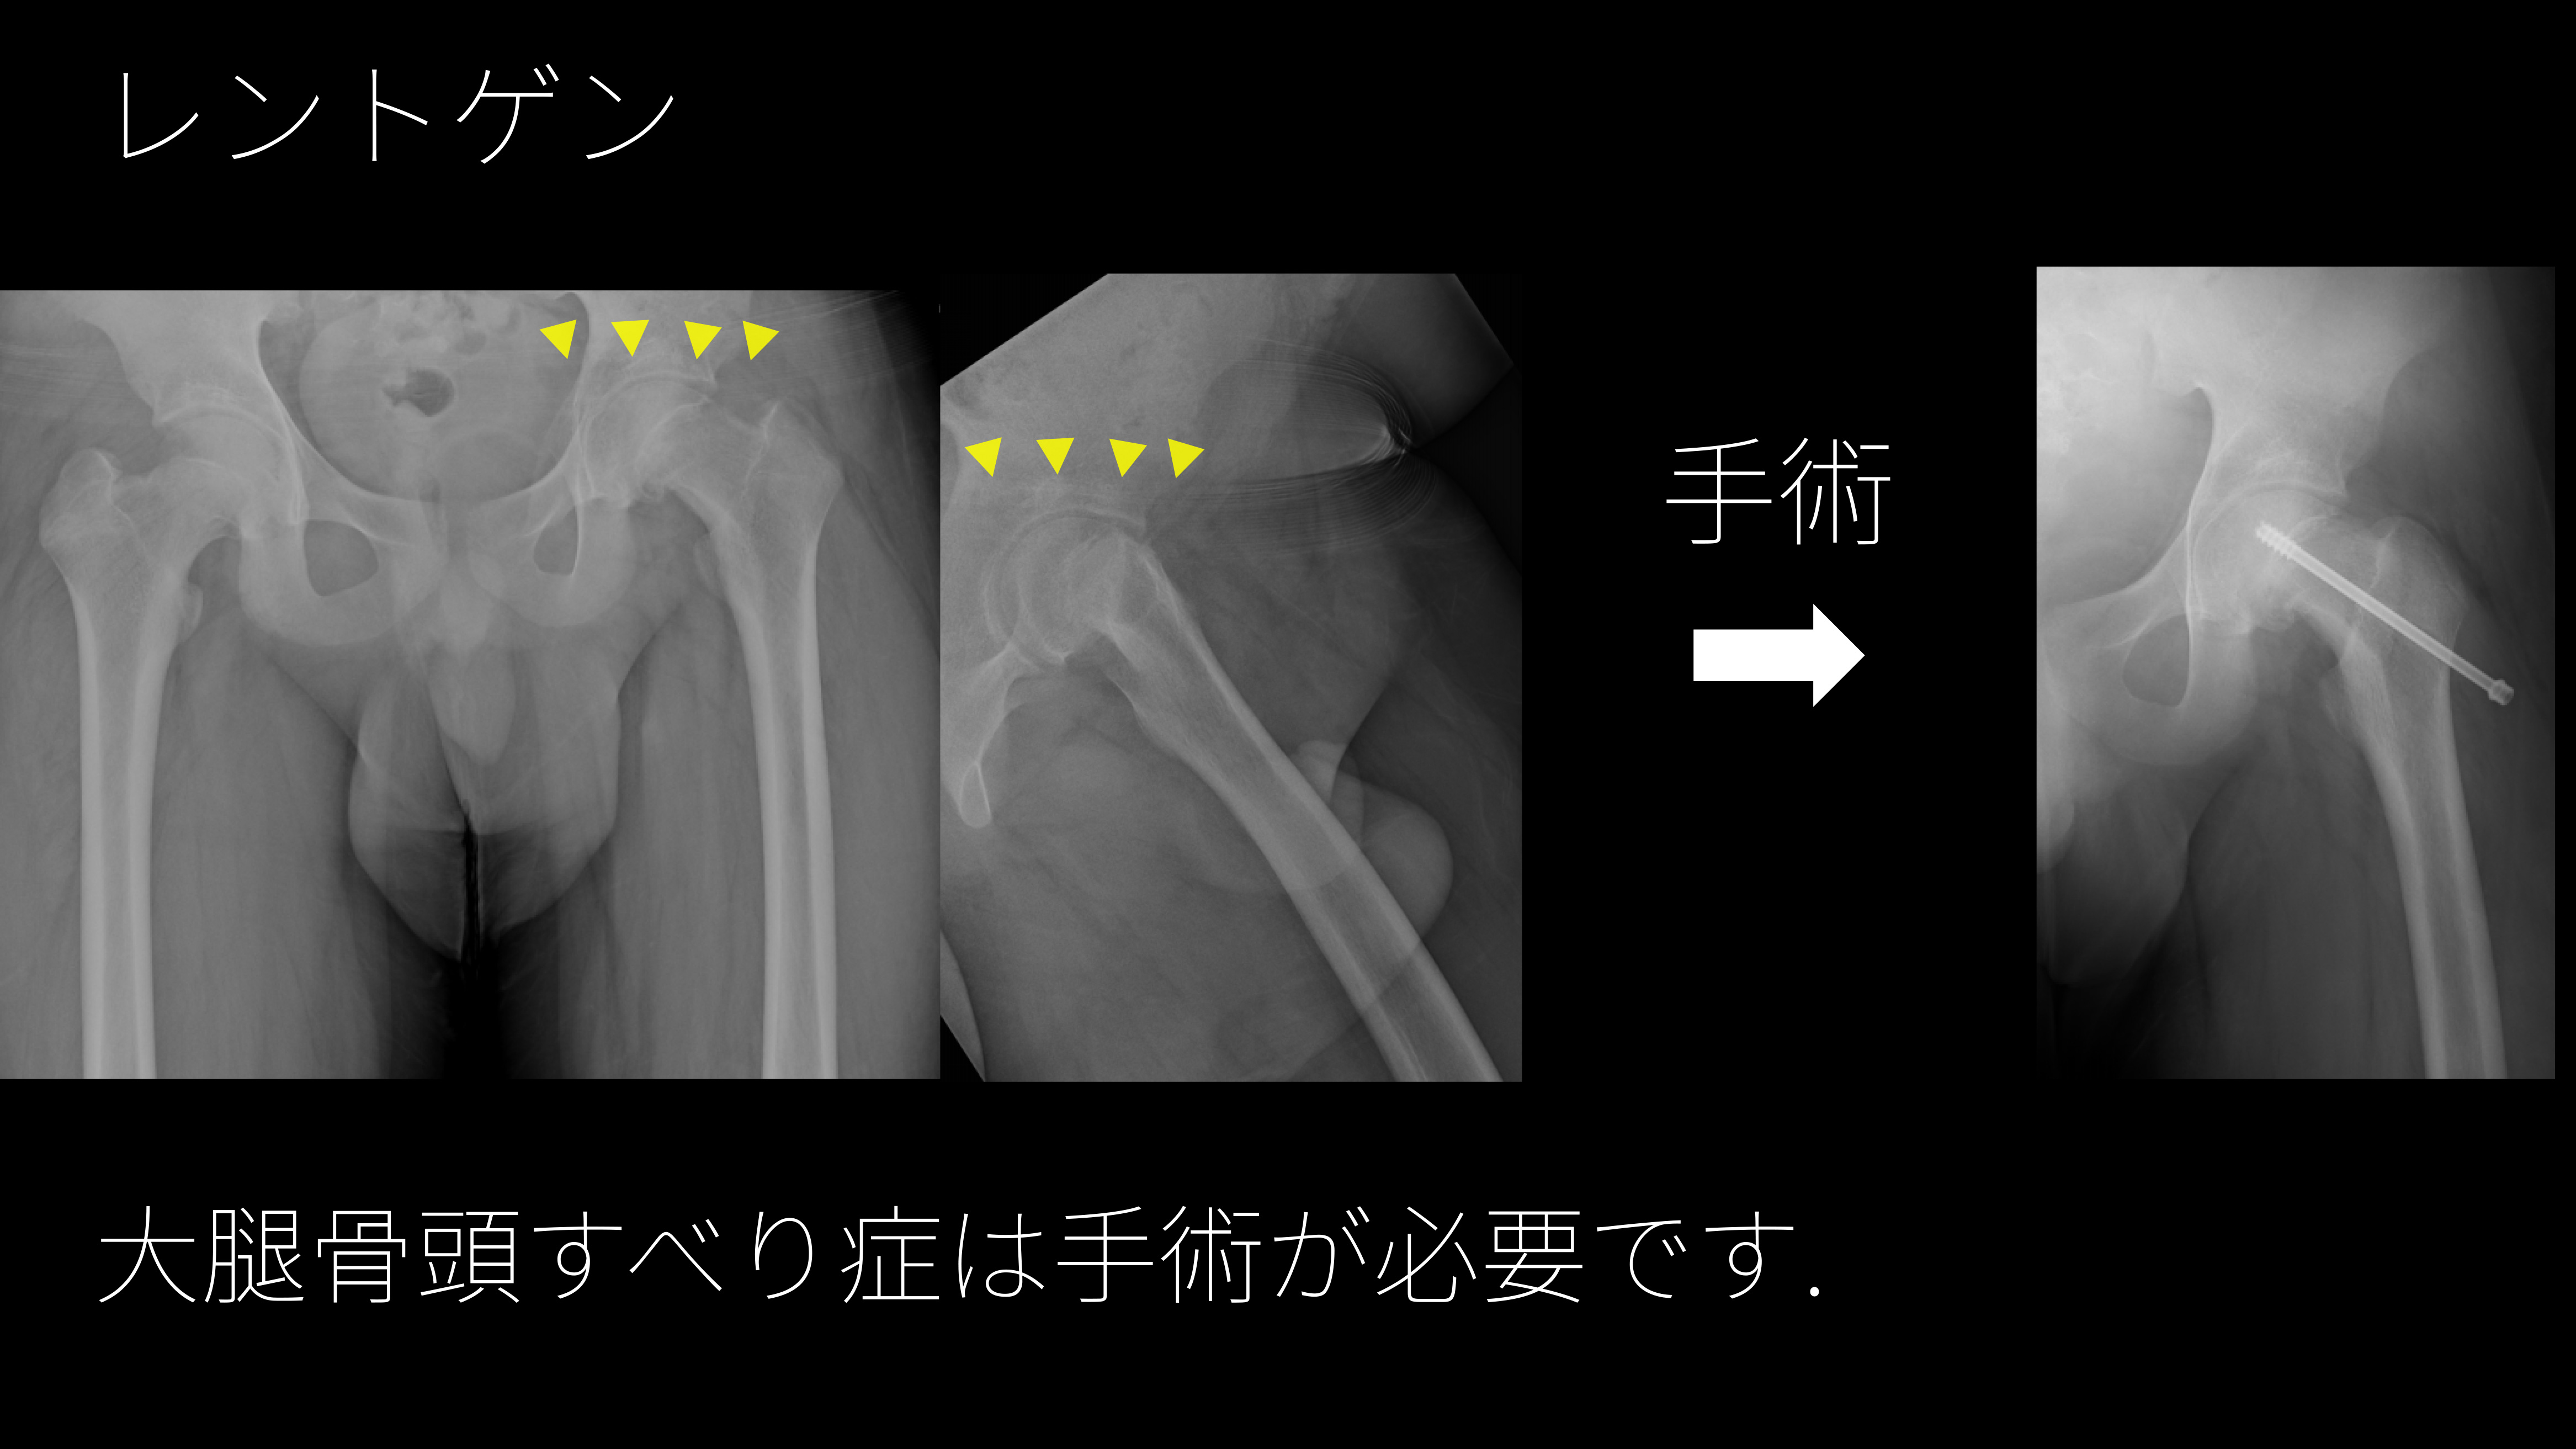

左の大腿骨頭すべり症の患者です。

左はいわゆるガニマタ、つま先を外に向けて歩いています。

足をつくときに、左肩が下がっています。

骨の成長線のところ(矢印)で大腿骨頭がずれることで痛みや跛行の原因となります。

股関節ではなく太ももや膝が痛いことがあります。

レントゲンが診断の役に立ちます。

男児は11~14歳、女児は10~12歳頃に多いといわれています。

肥満や過度のスポーツ活動が原因となることが多いです.